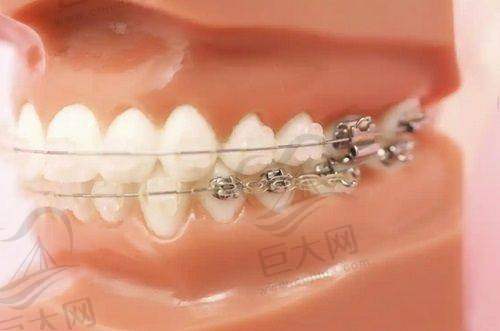

牙齿矫正也是医院的重点项目,常见的有龅牙矫正、地包牙矫正、虎牙矫正、牙齿不齐矫正、隐形正畸等。不同的矫正方式适用于不同的牙齿问题,医生会根据患者的具体情况制定个性化的矫正方案。

矫正牙齿可以改善牙齿的排列和咬合关系,不仅能提升美观度,还对口腔健康有益。矫正过程可能需要一定的时间和耐心,患者需要按照医生的要求佩戴矫正器,并定期复诊。